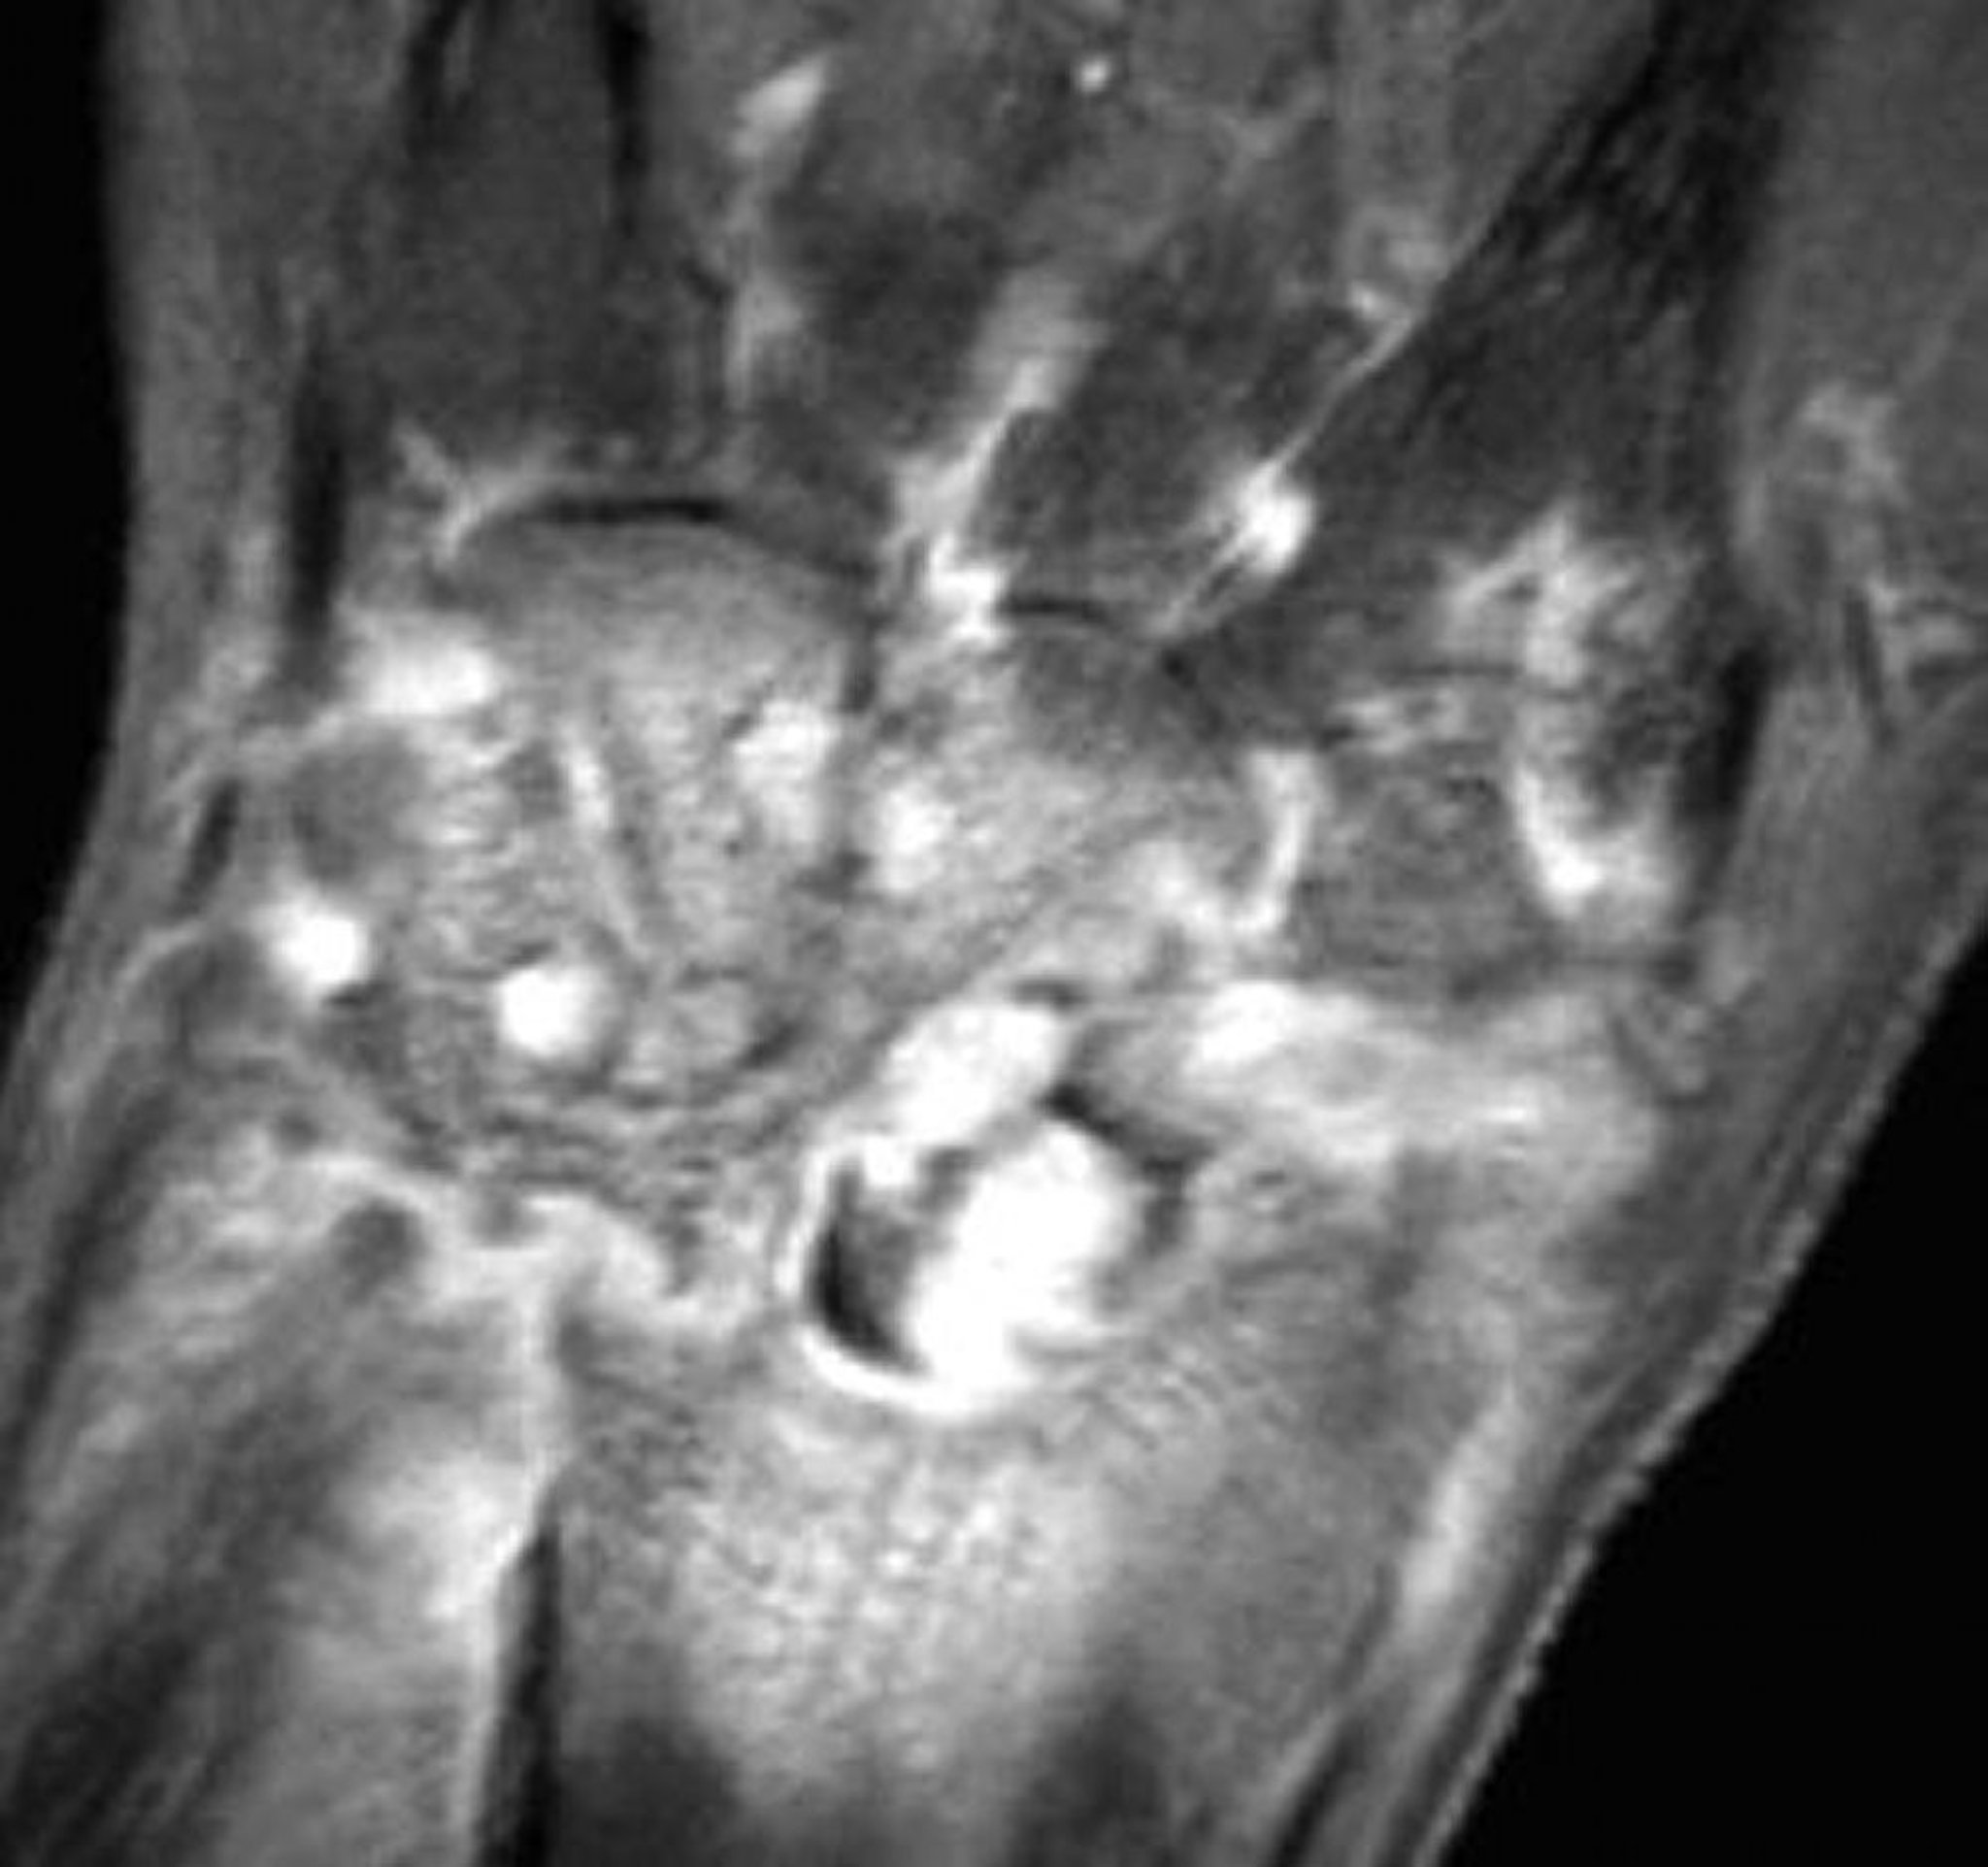

RM de artritis gonocócica en la muñeca

Esta RM coronal con supresión grasa ponderada en T1 con gadolinio de una muñeca con artritis séptica gonocócica muestra realce sinovial difuso y erosiones.